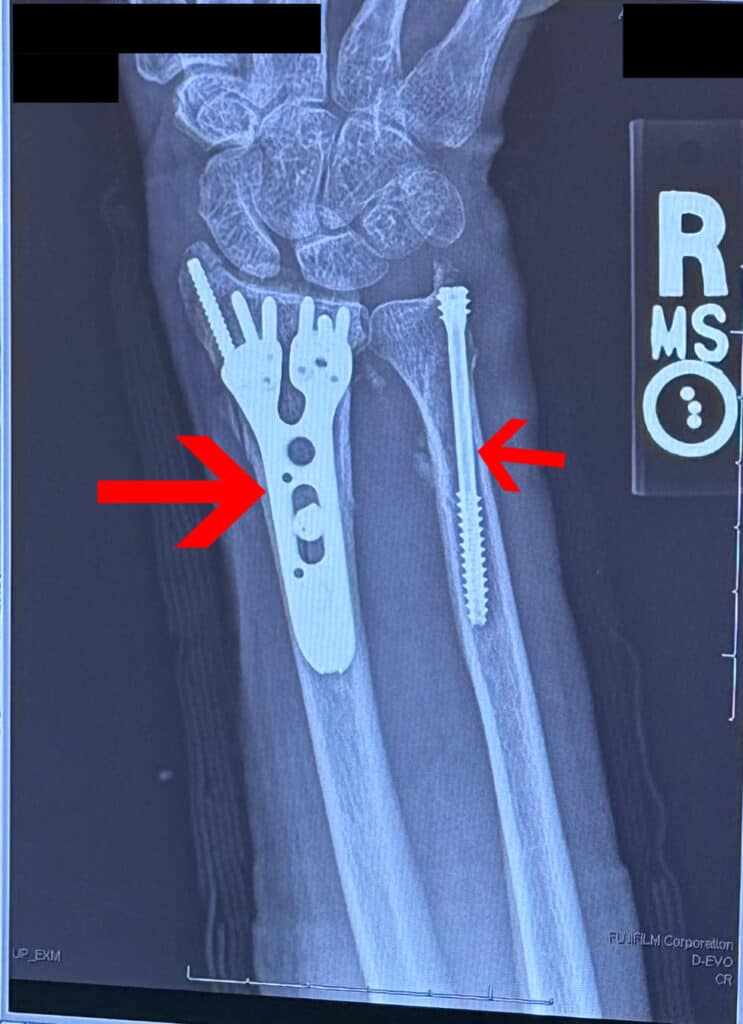

The crash happened when another driver suddenly tried to make a turn across Maria’s lane at an intersection in Pembroke Pines. Maria had the green light, but there was no time to stop. The impact crushed the front of her car and left her with a fractured wrist, ruptured breast implants, and a head injury.

Maria’s left hand was in a cast after surgery, and even simple things like buttoning a shirt or washing her hair were a struggle. Still, she pushed through while we began tracking down every lead we could find.